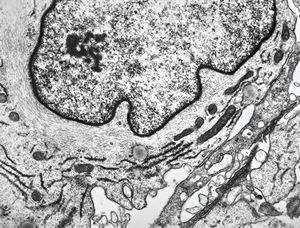

M, 70y. | mycosis fungoides - Sézary cell